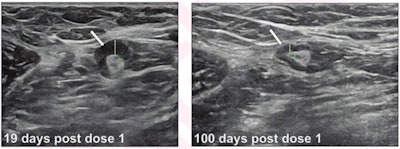

A team led by Dr. Michele Drotman from Weill Cornell Medicine in New York City found in their single-center study of 111 patients that lymphadenopathy detected by breast ultrasound resolved on its own after an average of 97 days since detection and 127 days since the first dose. The team also found longer resolution times with Moderna vaccination, receipt of a second vaccine dose after presentation, and thicker cortical thickness at presentation.

The researchers wrote that these results support a follow-up interval of at least 12 weeks for suspected vaccine-related lymphadenopathy, as well as avoiding screening mammography delays after vaccination.